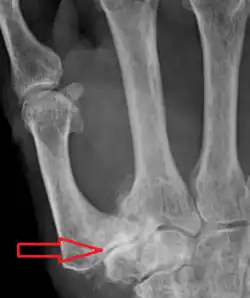

Stage 4 trapeziometacarpal osteoarthritis, with major subluxation of the joint

Stage 4:

• Narrow joint space

• Concomitant scaphotrapezial arthritis

X-ray of trapeziometacarpal joint replacement. Left hand of a 58-year-old woman.